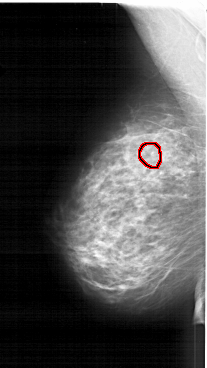

A_1259_1.LEFT_MLO

LEFT_MLO LINES 5881 PIXELS_PER_LINE 3301 BITS_PER_PIXEL 12 RESOLUTION 43.5 OVERLAY

FILE: A_1259_1.LEFT_MLO.OVERLAY

TOTAL_ABNORMALITIES 1

ABNORMALITY 1

LESION_TYPE CALCIFICATION TYPE PLEOMORPHIC DISTRIBUTION CLUSTERED

ASSESSMENT 4

SUBTLETY 2

PATHOLOGY BENIGN

TOTAL_OUTLINES 1

BOUNDARY